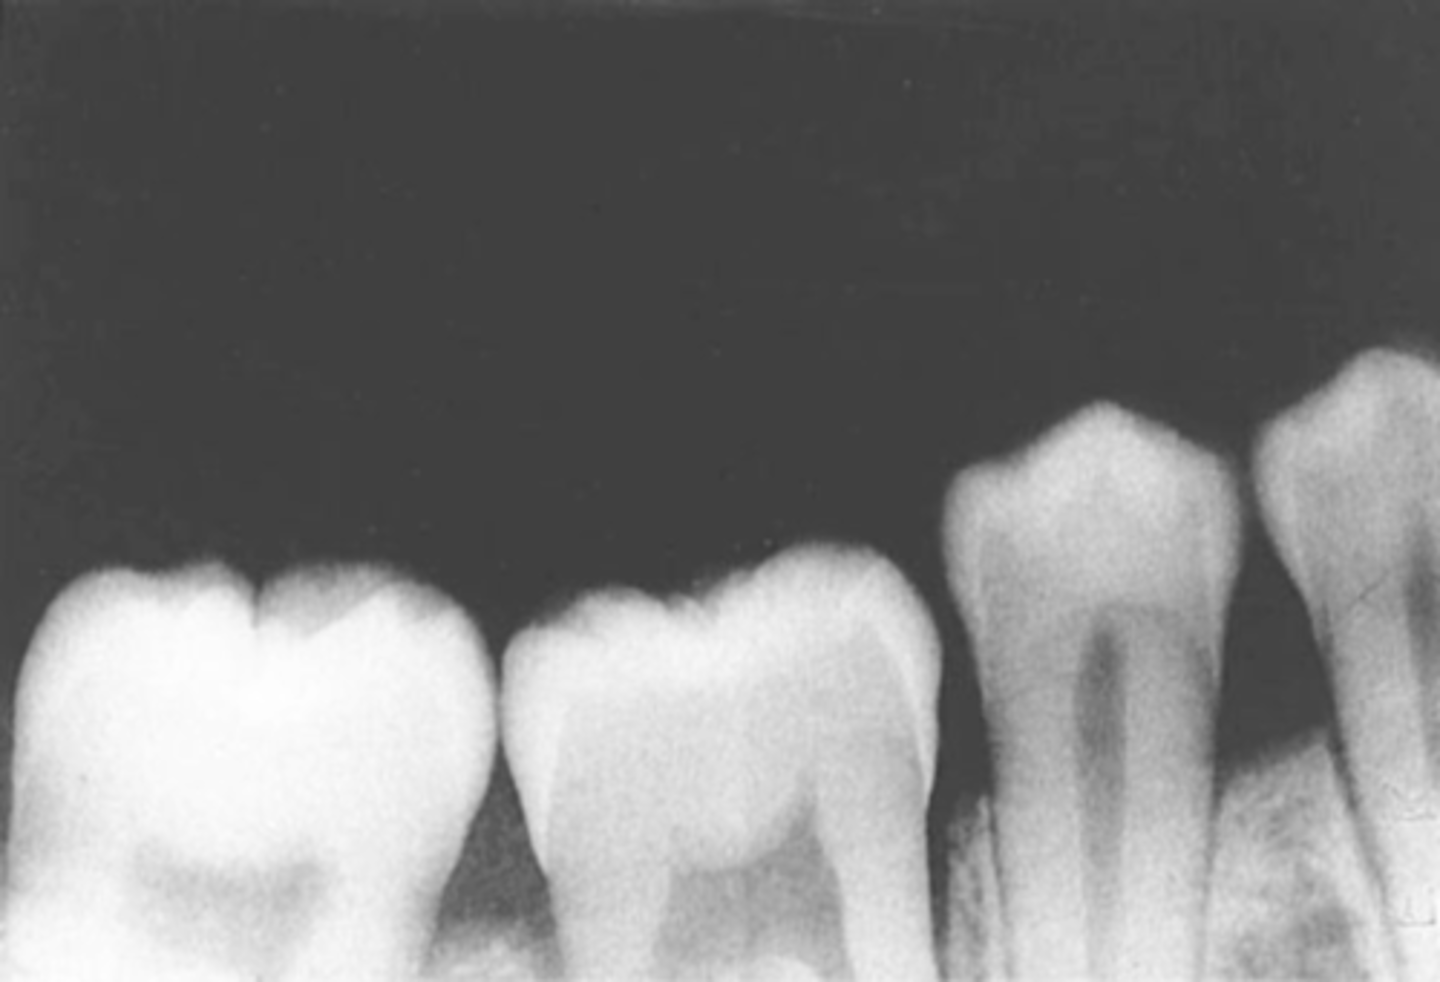

Overlapped Contacts

On a dental image, the area where the contact area of one tooth is superimposed over the contact area of an adjacent tooth

Incorrect Horizontal Angulation

-Overlapped contacts

-CR was not directed through the interproximal spaces, resulting in the proximal surfaces of adjacent teeth appear overlapped in the PA.

-Occurs in both paralleling and bisecting technique

-To prevent direct the x-ray beam through the interproximal regions

Incorrect Horizontal Angulation -->Bite-Wing

-CR was not directed through the interproximal spaces.